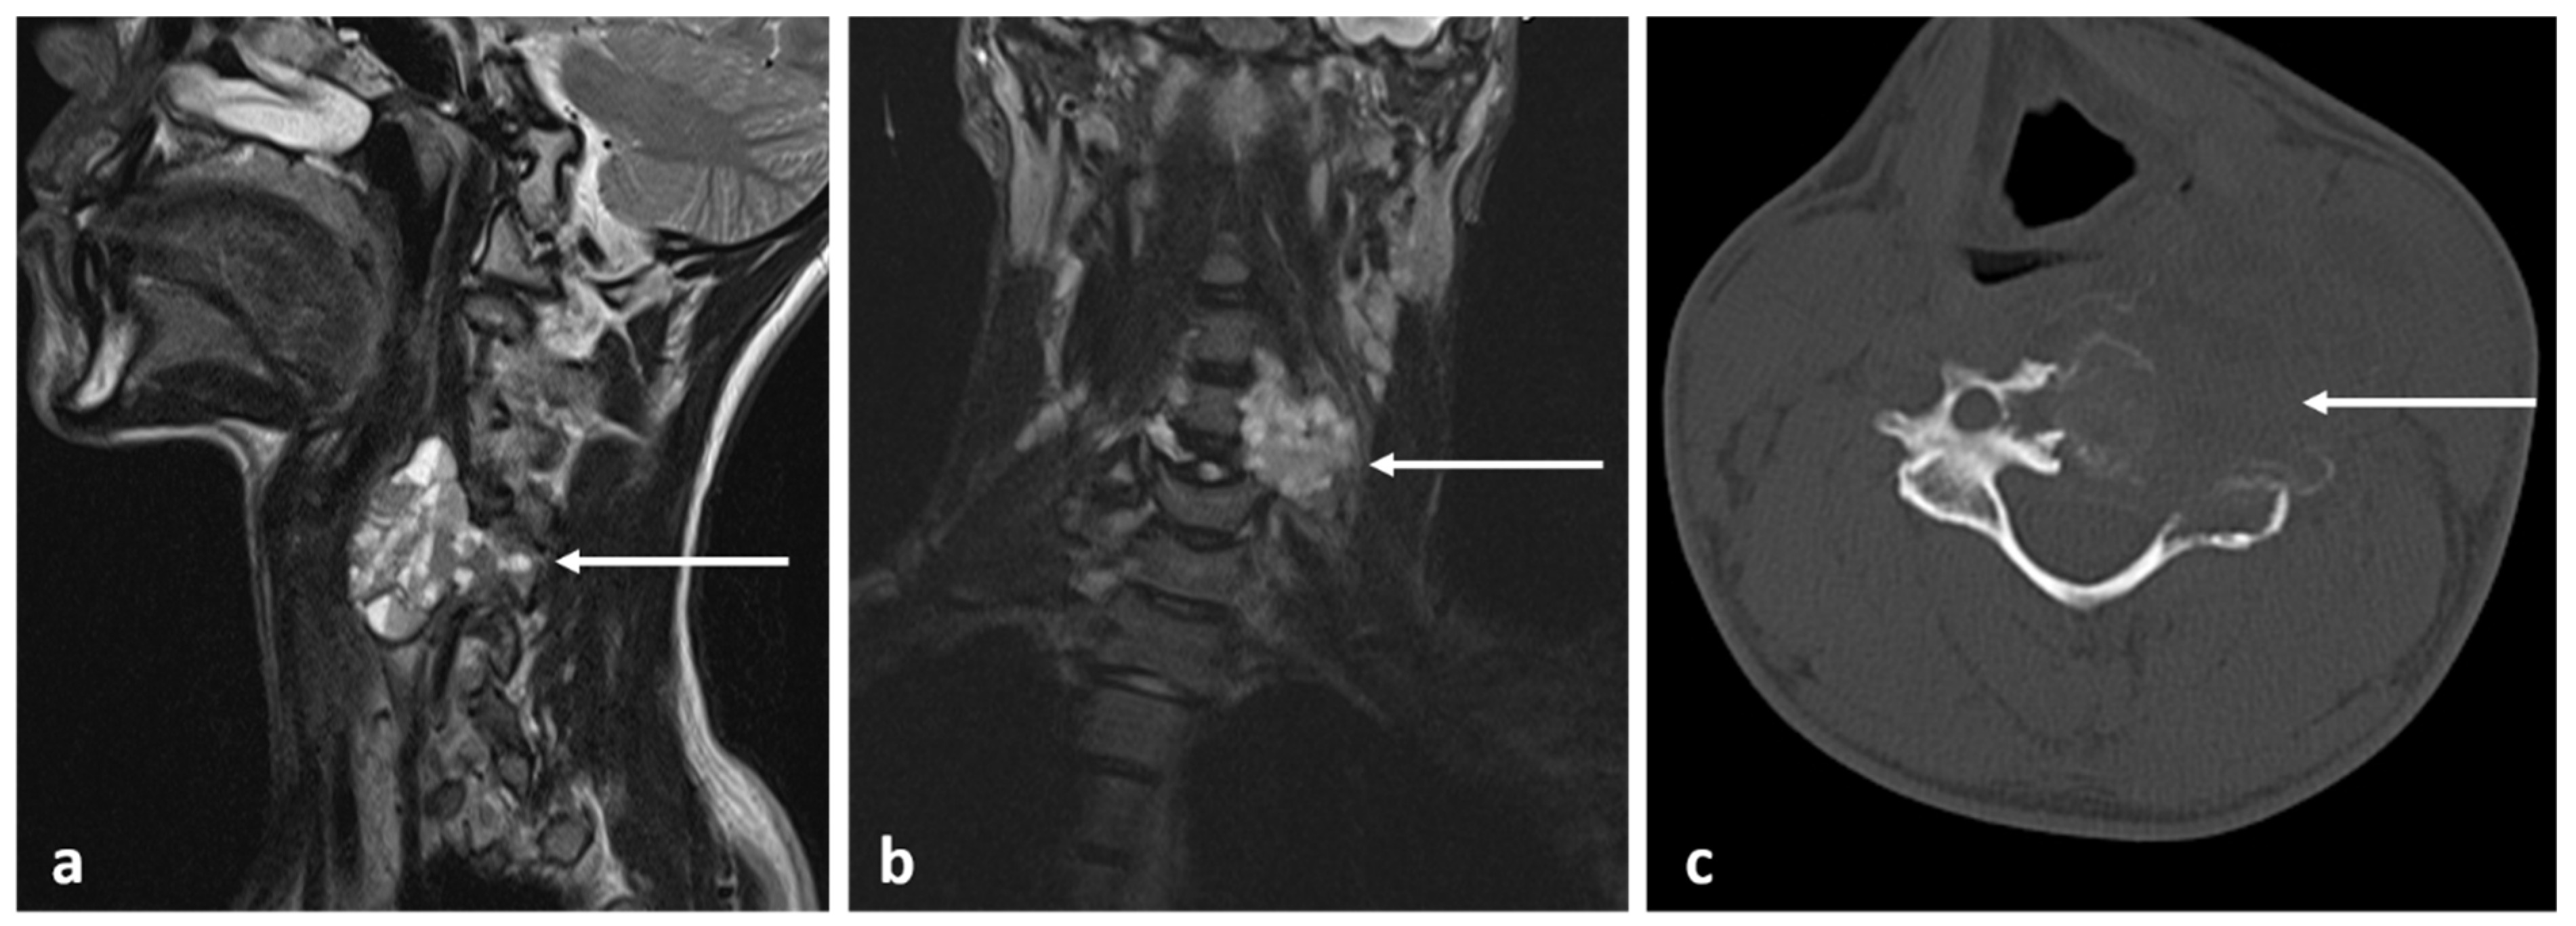

3.6. Chondroblastoma

- Rajakulasingam, R.; Murphy, J.; Botchu, R.; James, S.L. Osteochondromas of the cervical spine-case series and review. J. Clin. Orthop. Trauma. 2020, 11, 905–909. [Google Scholar] [CrossRef]

| Osteoblastoma | Expansile lucent lesion. Sclerotic rim. Bone destruction. Variable intralesional ossification. | Low to intermediate T1 signal and intermediate to high T2 signal. Surrounding soft tissue oedema, extra osseous soft tissue component. |

| Osteochondroma | Lesion continuity with cortex and medulla. | Cartilage cap |

| Chondroblastoma | Osteolytic lesion. Variable intralesional calcification (chondroid matrix) | Extraosseous soft tissue component |